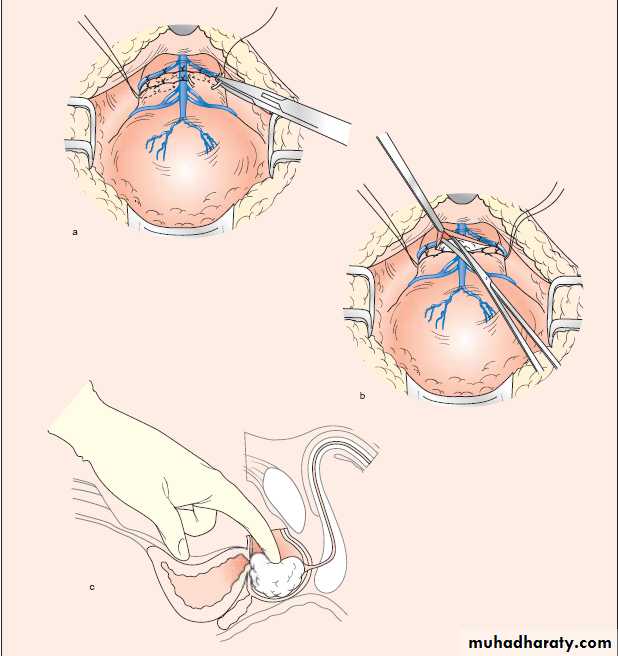

Retropubic prostatectomy

30

Transvesical prostatectomy

31